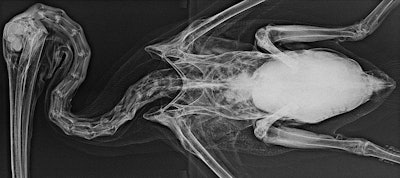

But ultrasound may be impossible in some situations and even some species, such as marine birds with subcutaneous emphysema. In that case, ionizing radiation is preferred, and, as with humans, x-rays tend to work best for imaging of bones and lungs. Classical radiography is easily accessible and available in most aquariums, and it's easy to interpret. It's the preferred modality in birds.